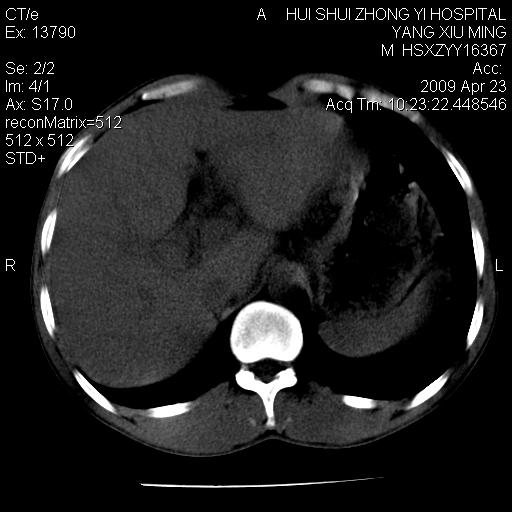

上腹部疼痛一月,呕吐10天,发现左侧颈部包快10天 胸部cr片未见明显异常。

腹膜后淋巴结增大,转移、淋巴瘤?胰腺增大,胰腺炎?占位?颈部考虑增大淋巴结。建议腹部增强扫描。

图像黑了点!

连最基本的ct值都没有测        腹部的窗宽窗位太大了     影响诊断

黑!广泛淋巴结肿大不符合胰腺癌转移。胰腺周围淋巴结肿大致使胰腺看起来大。考虑淋巴瘤可能大。